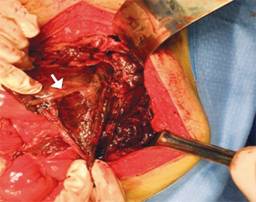

Figura 4: Imagen transoperatoria que muestra necrosis gástrica generalizada y perforación de 4 cm a nivel de su curvatura mayor (flecha).